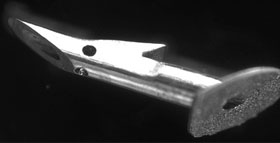

Ex-press